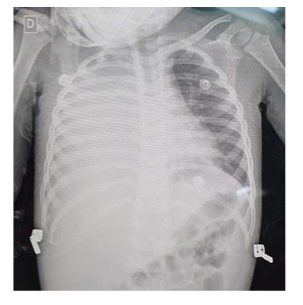

Uma menina de um ano e sete meses de idade foi levada ao pronto-socorro com queixa de dor abdominal, vômitos e febre (39 ⁰C) há dois dias. Sua mãe referia resfriado há dez dias, com piora há três dias. Exame físico: REG; descorada 2 +/4+; anictérica; acianótica; afebril; taquipneica; FR de 50 irpm; FC de 140 bpm; PA de 85 x 50 mmHg; sat. de O2 de 91% em ar ambiente; MV+, abolido em 2/3 inferiores do hemitórax direito; broncofonia diminuída em base direita; e tiragem subcostal. Exames: Hb 9.5 g/dl; Ht 27%; leucócitos 26.500, com desvio à esquerda; e PCR 25 mg/dl.